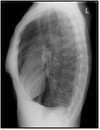

What pathology is seen here?

A

Cystic fibrosis

Lung looks scratchy